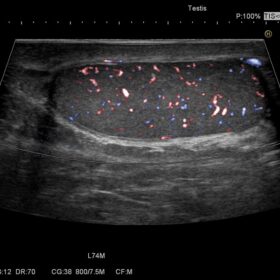

Ultrasound HI VISION Avius – Image Gallery and Videos

Radiology 2D, Color, PW and Elasto mode